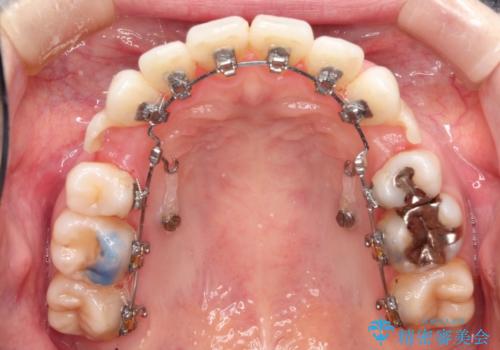

裏側のワイヤー矯正 抜歯して前歯をしっかり後ろに下げる

- リンガル

上顎の、前から4番目の歯を左右1本ずつ抜歯して前歯を後方に下げる計画としました。

目立たずに矯正をご希望でしたので、裏側矯正で治療を行いました。